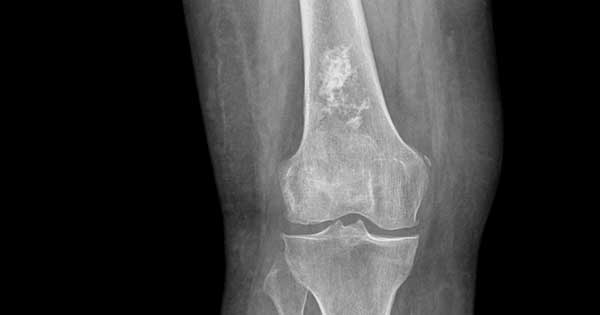

Los condrosarcomas son un tipo de tumor maligno que se caracterizan por su crecimiento lento y la producción de matriz cartilaginosa. Estos tumores se desarrollan principalmente en el esqueleto axial,…